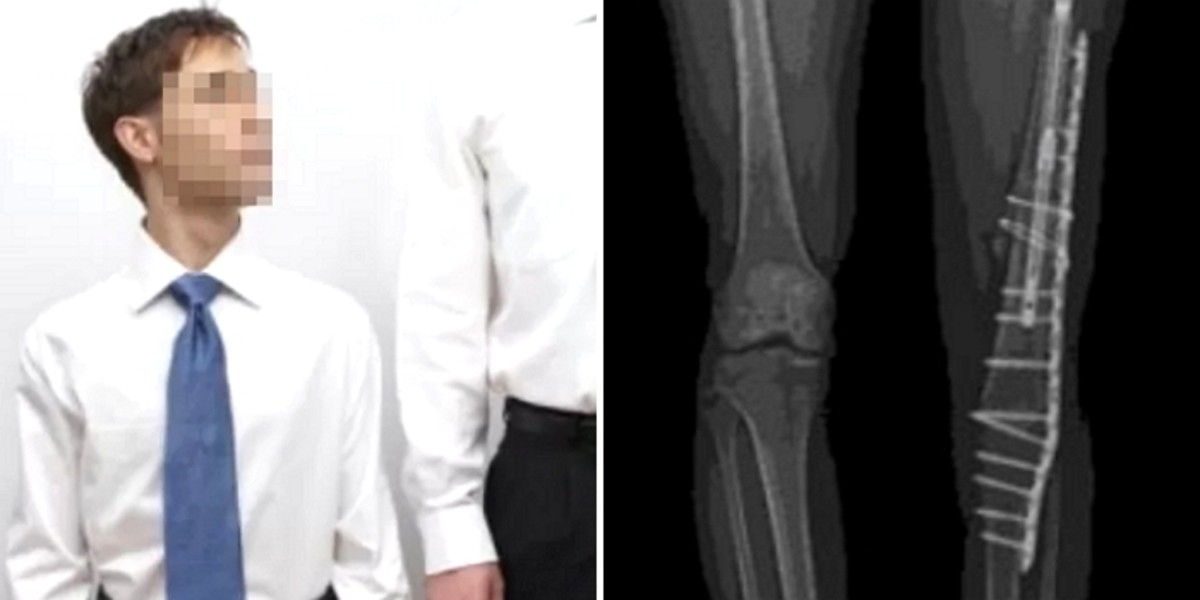

인사이트기사의 이해를 돕기 위한 사진 / gettyimagesBank